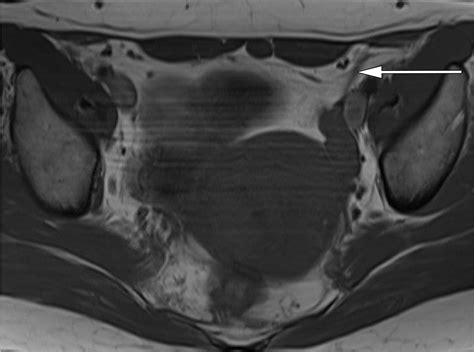

• Imaging Studies: Ultrasound, CT scan, and MRI are commonly used to visualize the ovaries, fallopian tubes, and surrounding ligaments. These imaging techniques can help identify abnormalities such as ovarian torsion, PID, or endometriosis.